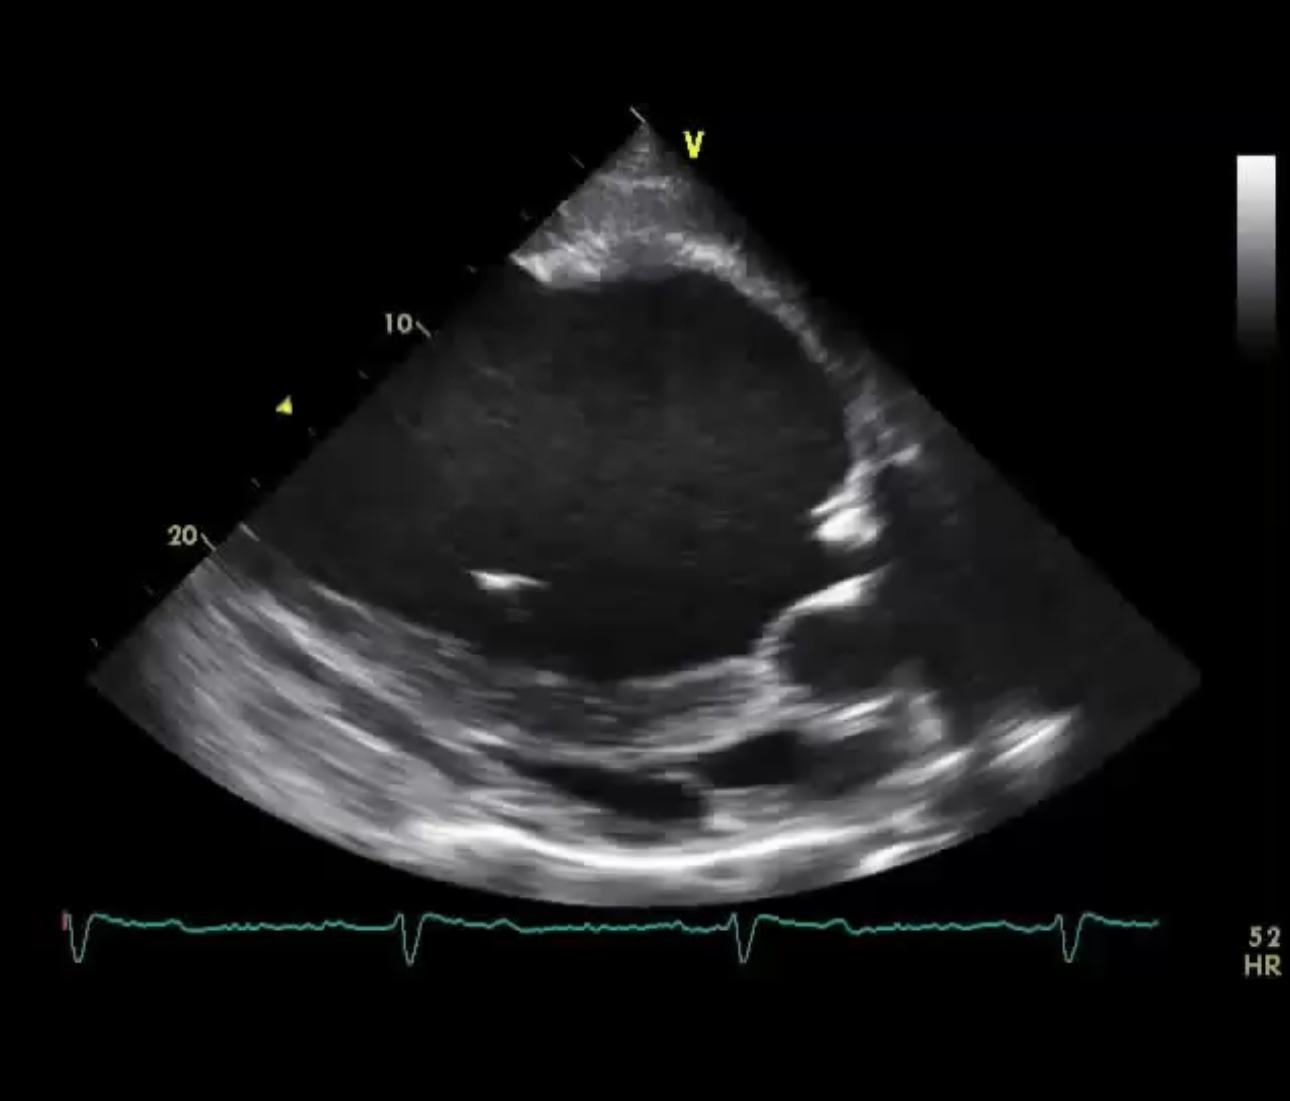

- Darstellung des Herzens (in verschiedenen Ebenen) und des Blutflusses

- nicht vollständig schließende Aortenklappe sichtbar

- pathologische Verwirbelungen des Blutflusses

- nach Messung Vergrößerung der linken Herzkammer

Diagnose: hochgradie Aortenklappeninsuffizienz, mittelgradige Vergrößerung linker Ventrikel (sekundär)

- „undichter“ Verschluss der Aortenklappe, Rückfluss von Blut aus Aorta in die linke Herzkammer